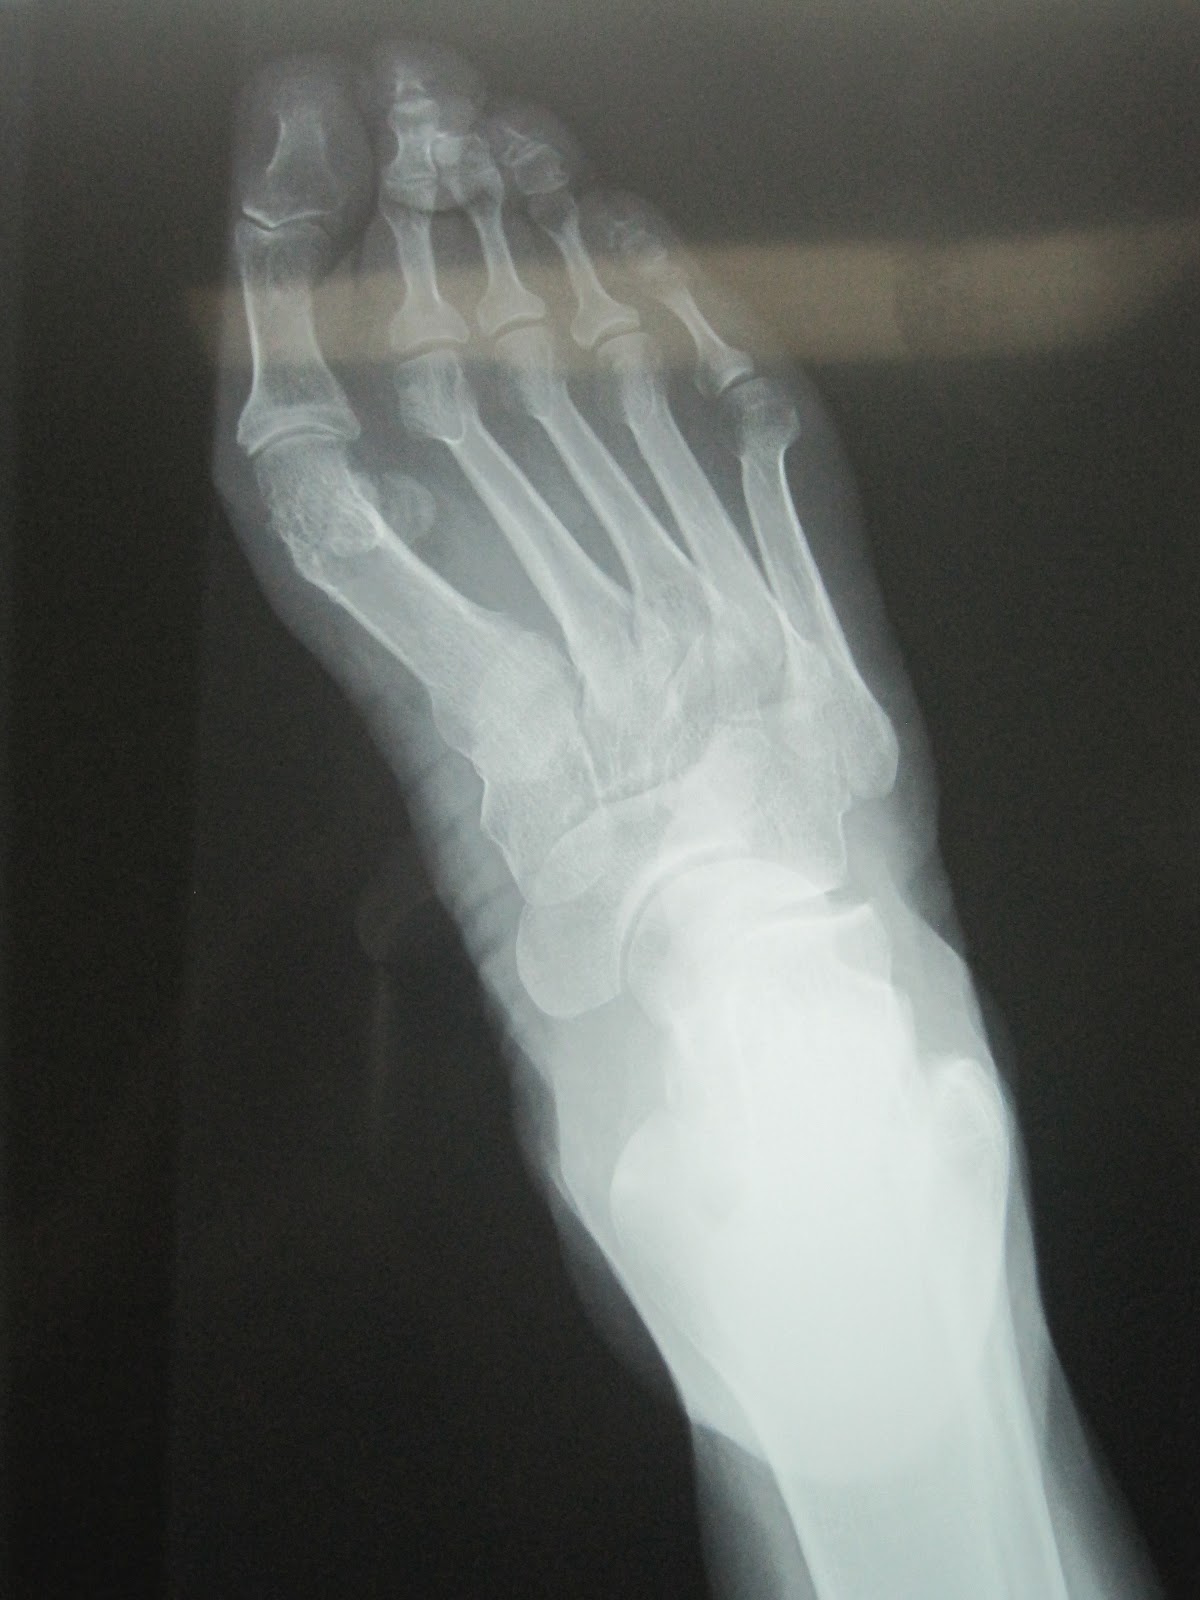

El pie era algo complicado, como podéis ver en la foto. Fijaros en los dedos, fijaros en el juanete. La mujer tiene 50 años y dolores en la planta.

Fijaros en las siguientes radiografías, la elevación del primer metatarsiano, el segundo meta largo, dedos en garra.

Aquí podemos ver el ángulo intermetatarsiano muy abierto, lo cual, en la operación anterior no corrigieron, los sesamoideos luxados, el primer dedo en varo, insuficiencia de primer radio, segundo radio con sorbrecarga y bastante mas largo, segundo dedo infraductus, en ráfaga y supraductus sobre el tercero.

Podemos ver también un hallux varus y el 5º dedo infraductus bajo el cuarto.

Sobrecarga del segundo y tercer metatarsianos. Debajo de la cabeza del segundo metatarsiano es donde mas le duele, tan solo con la presión del dedo, la paciente se quejaba.

Ahora muestro las radiografía de como quedó ese pie. Esta es la foto de la radiografía preoperatoria. Fijaros de nuevo en el primer dedo en valgo, la articulación metatarsofalángica del primer radio, el ángulo intermetatarsal de primero y segundo; la longitud del segundo metatarsiano y del primero, la colocación de los dedos, la luxación de los sesamoideos, etc.